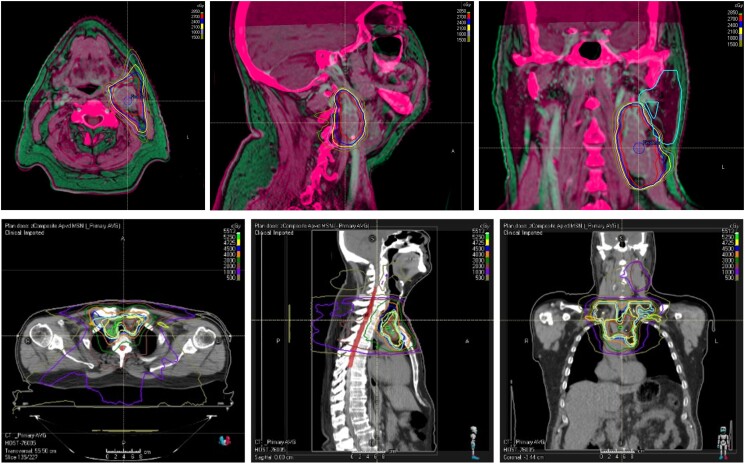

A 65-year-old patient presented with recurrent, locally advanced poorly differentiated thyroid cancer despite 2 neck surgeries, and with newly diagnosed brain and skull base metastases. He was treated with palliative stereotactic radiosurgery to the brain and skull base lesions. Thereafter, as no targetable genetic alteration was identified and antiangiogenic multikinase inhibitors were deemed at high risk of hemorrhagic complications, off-label systemic therapies were considered. The mechanistic target of rapamycin (mTOR) inhibitor everolimus could not be obtained due to lack of insurance coverage, so the patient was treated with single-agent pembrolizumab. He showed an initial remarkable response, but unfortunately had disease progression in the neck and upper mediastinum after 1 year of therapy. At that time, he was treated with external beam radiotherapy, with concomitant pembrolizumab. He was then found to have an CTSB::ALK fusion, which has previously been described in 2 cases of thyroid cancer. However, as he showed a positive response to radiation with pembrolizumab, he continued single-agent immune checkpoint inhibition and had a persistent marked response almost a year after completing radiation. The patient was then followed at an outside institution and was transitioned to hospice at time of progression per his preference. He died 4 years after his initial diagnosis.

Abstract Image